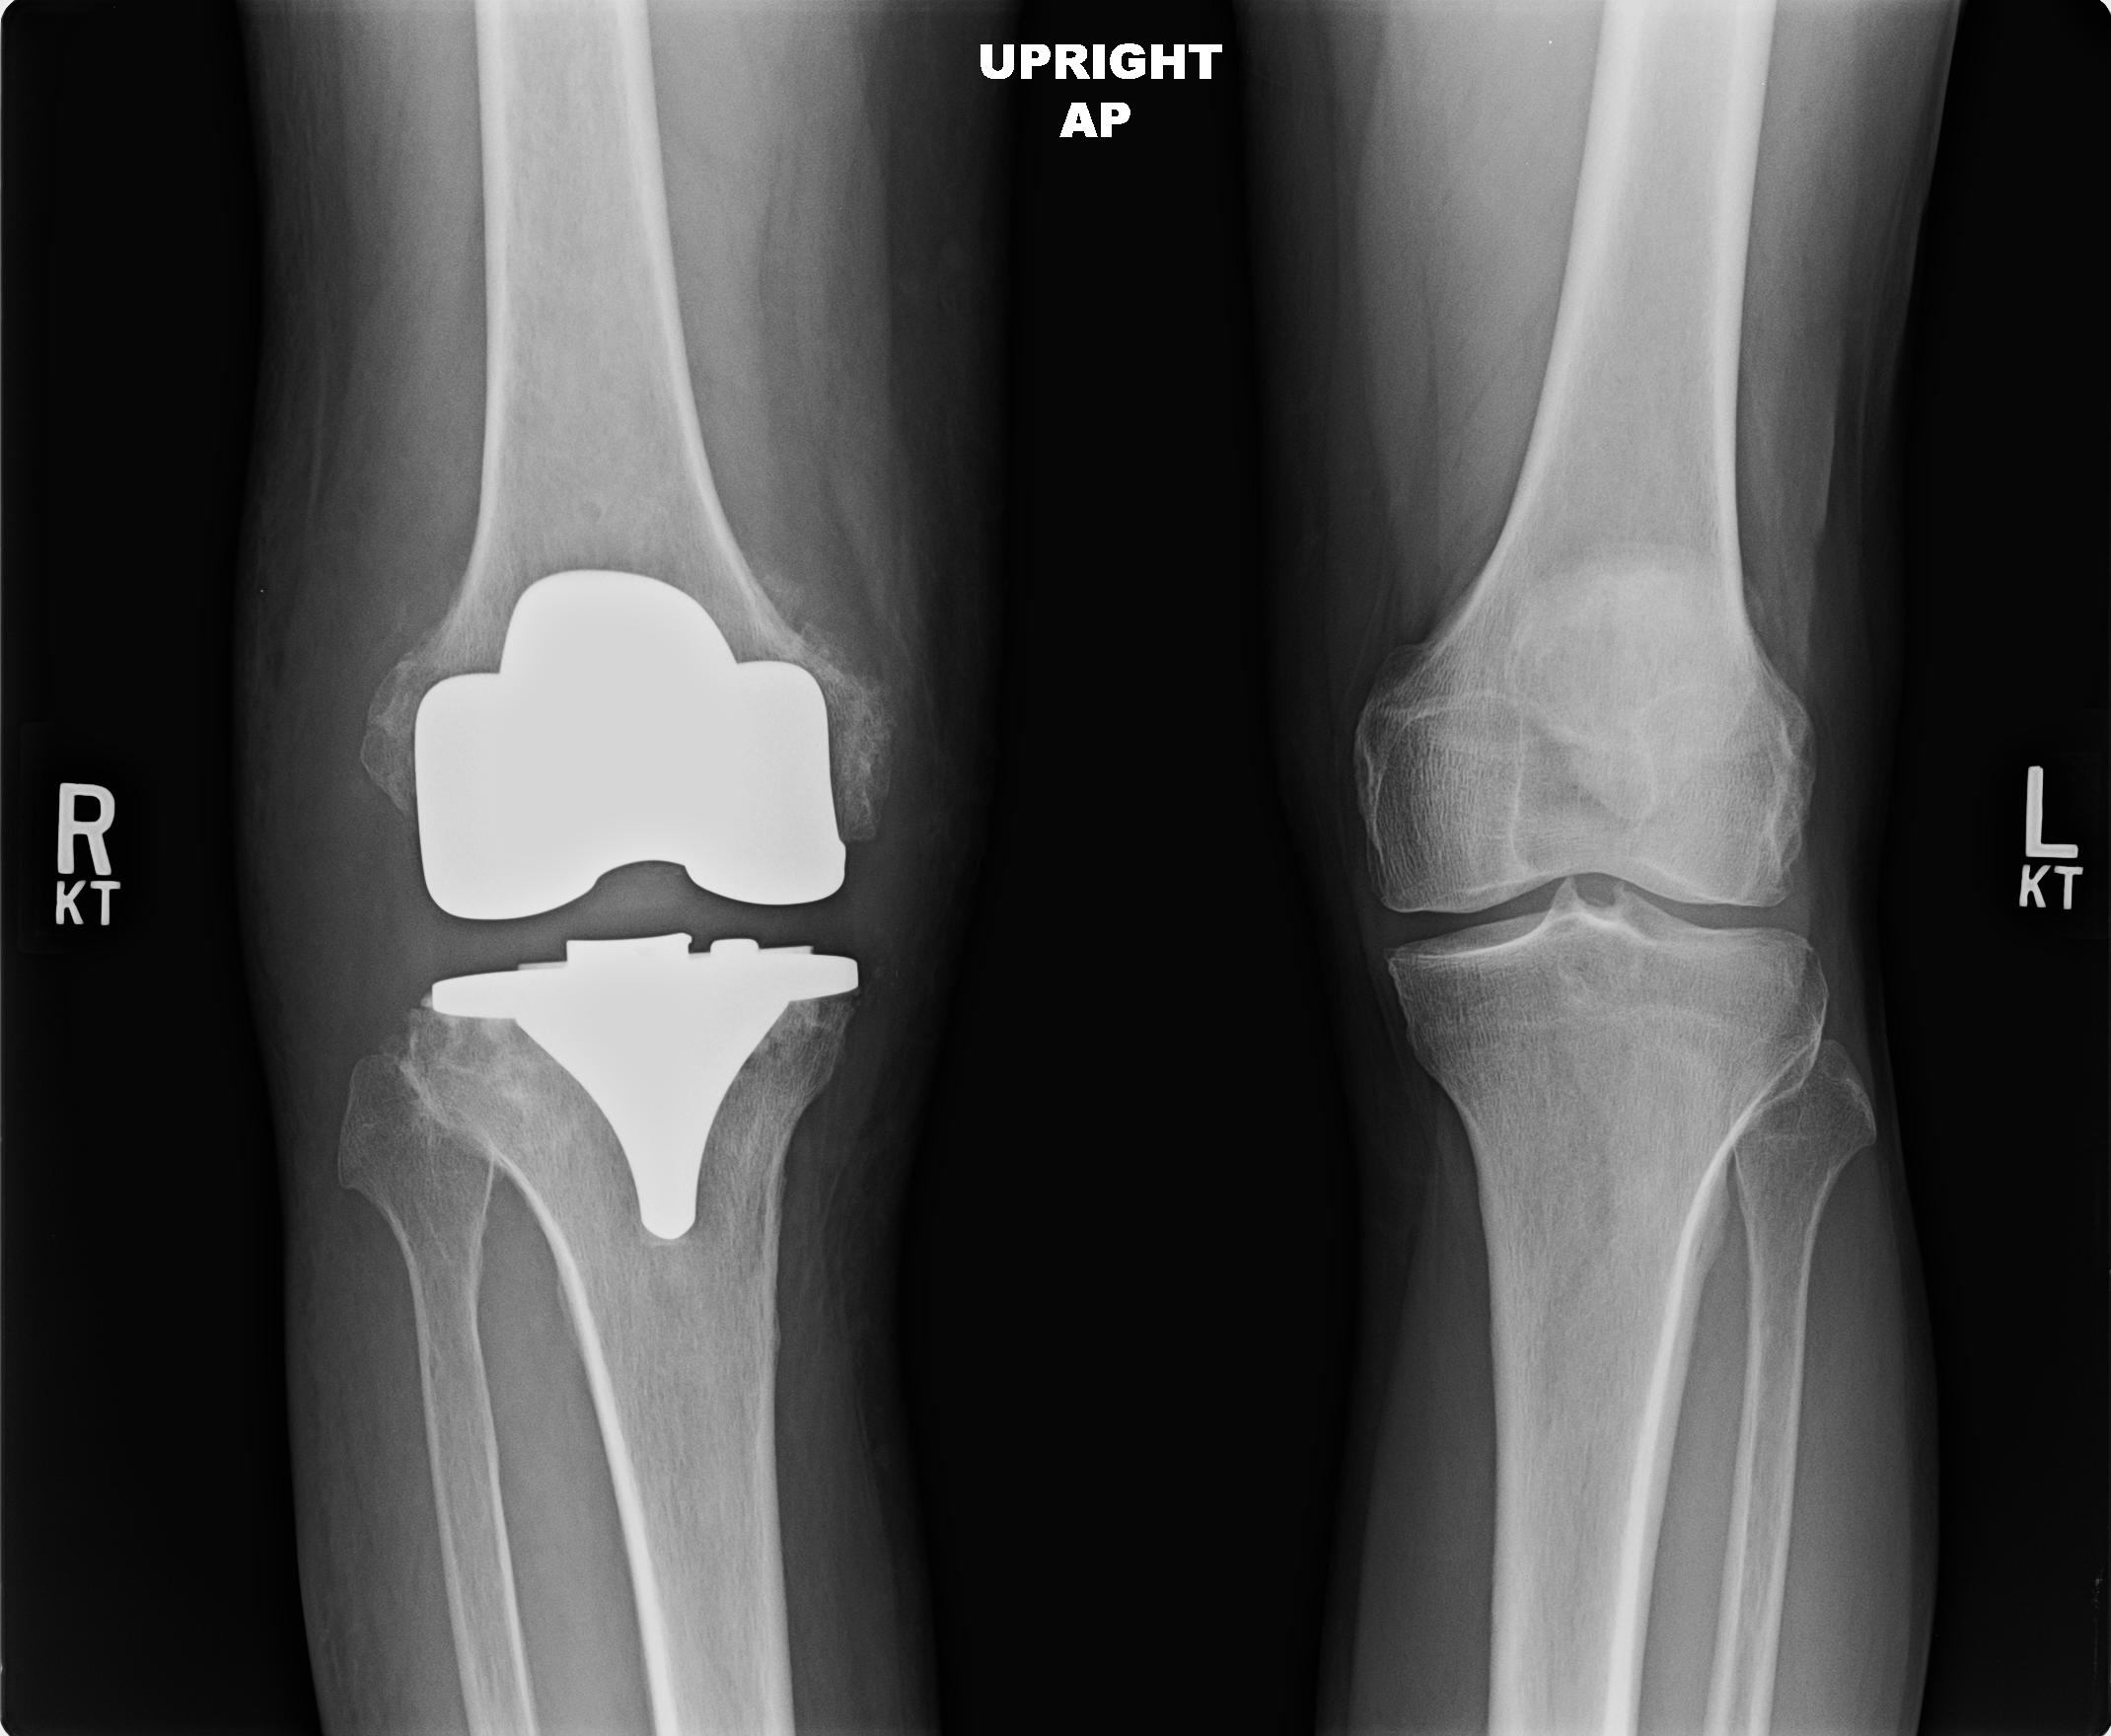

Αρθροπλαστική

Η αρθροπλαστική είναι η χειρουργική τεχνική που περιλαμβάνει την αφαίρεση μιας κατεστραμένης άρθρωσης και την αντικατάστασή της με μία τεχνητή. Η μέθοδος της αρθροπλαστικής διαφέρει ανάλογα με την άρθρωση στην οποία εφαρμόζεται (ισχίο, γόνατο, ώμος, αγκώνας, ποδοκνημική). Οι προθέσεις, τα εμφυτεύματα δηλαδή, που αντικαθιστούν τις κατεστραμένες αρθρώσεις είναι κατασκευασμένα από φιλικά για τον οργανισμό υλικά (μεταλλικά κράμματα, κεραμικά και πλαστικά).

X-ray